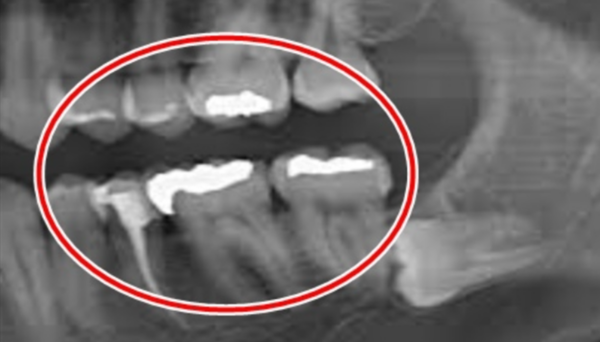

To, co následovalo, šokovalo nejen pacienta, ale i zkušeného zubního lékaře. Na rentgenovém snímku bylo vidět něco, co zubař ve své dlouholeté praxi nikdy předtím neviděl. Objevilo se tam něco, co by podle lékaře mohlo být zubem, ale realita byla mnohem složitější. Co odhalil lékař a jaké komplikace mohly nastat, kdyby pacient návštěvu zubaře ještě déle odkládal?